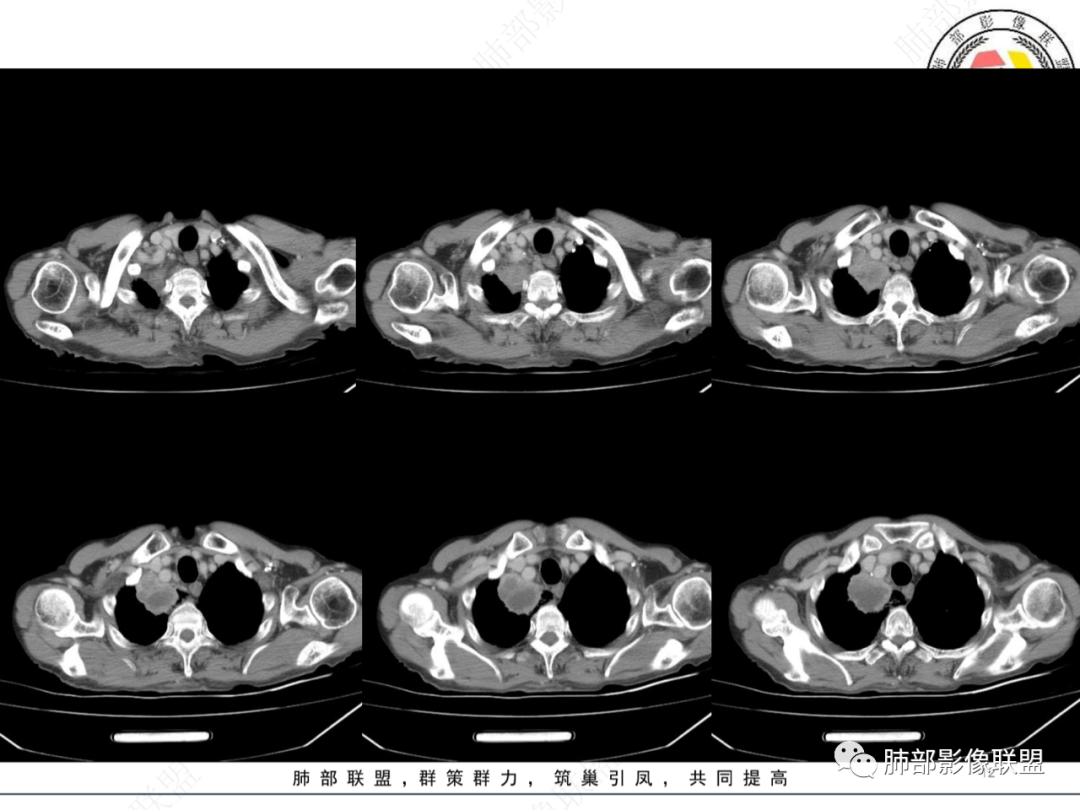

老年人,有高血压、脑梗死、肾结石病史

这次,半月,左胸痛不适,高热:39°C,白细胞、中性粒细胞高

右下叶背段有结节

南边 :

斑点

主病灶在右上叶尖段、前段纵隔旁,紧贴胸膜

楔形、边缘膨隆,附近见斑片状、网格状高密度影

支气管近端堵塞,可惜显示的不一定全面

支气管壁还是弥漫增厚

中央坏死明确